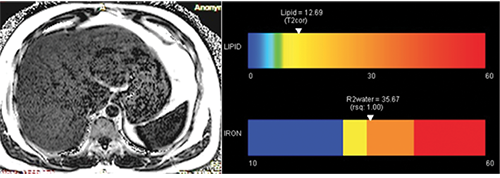

Liver fat quantification by MRI in a potential liver donor

Liver fat quantification by MRI in a potential liver donor. Image at left shows a liver fat fraction map; at right, a color display reveals the percentage of liver fat (lipid).